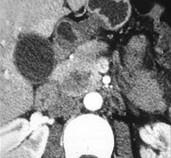

问题 女,56岁,腹部胀痛不适、食欲减退,影像表现如下图,最佳诊断是()

选项 A.急性胰腺炎 B.慢性胰腺炎 C.胰腺腺癌 D.胰腺转移癌 E.胰腺假性囊肿

答案 C